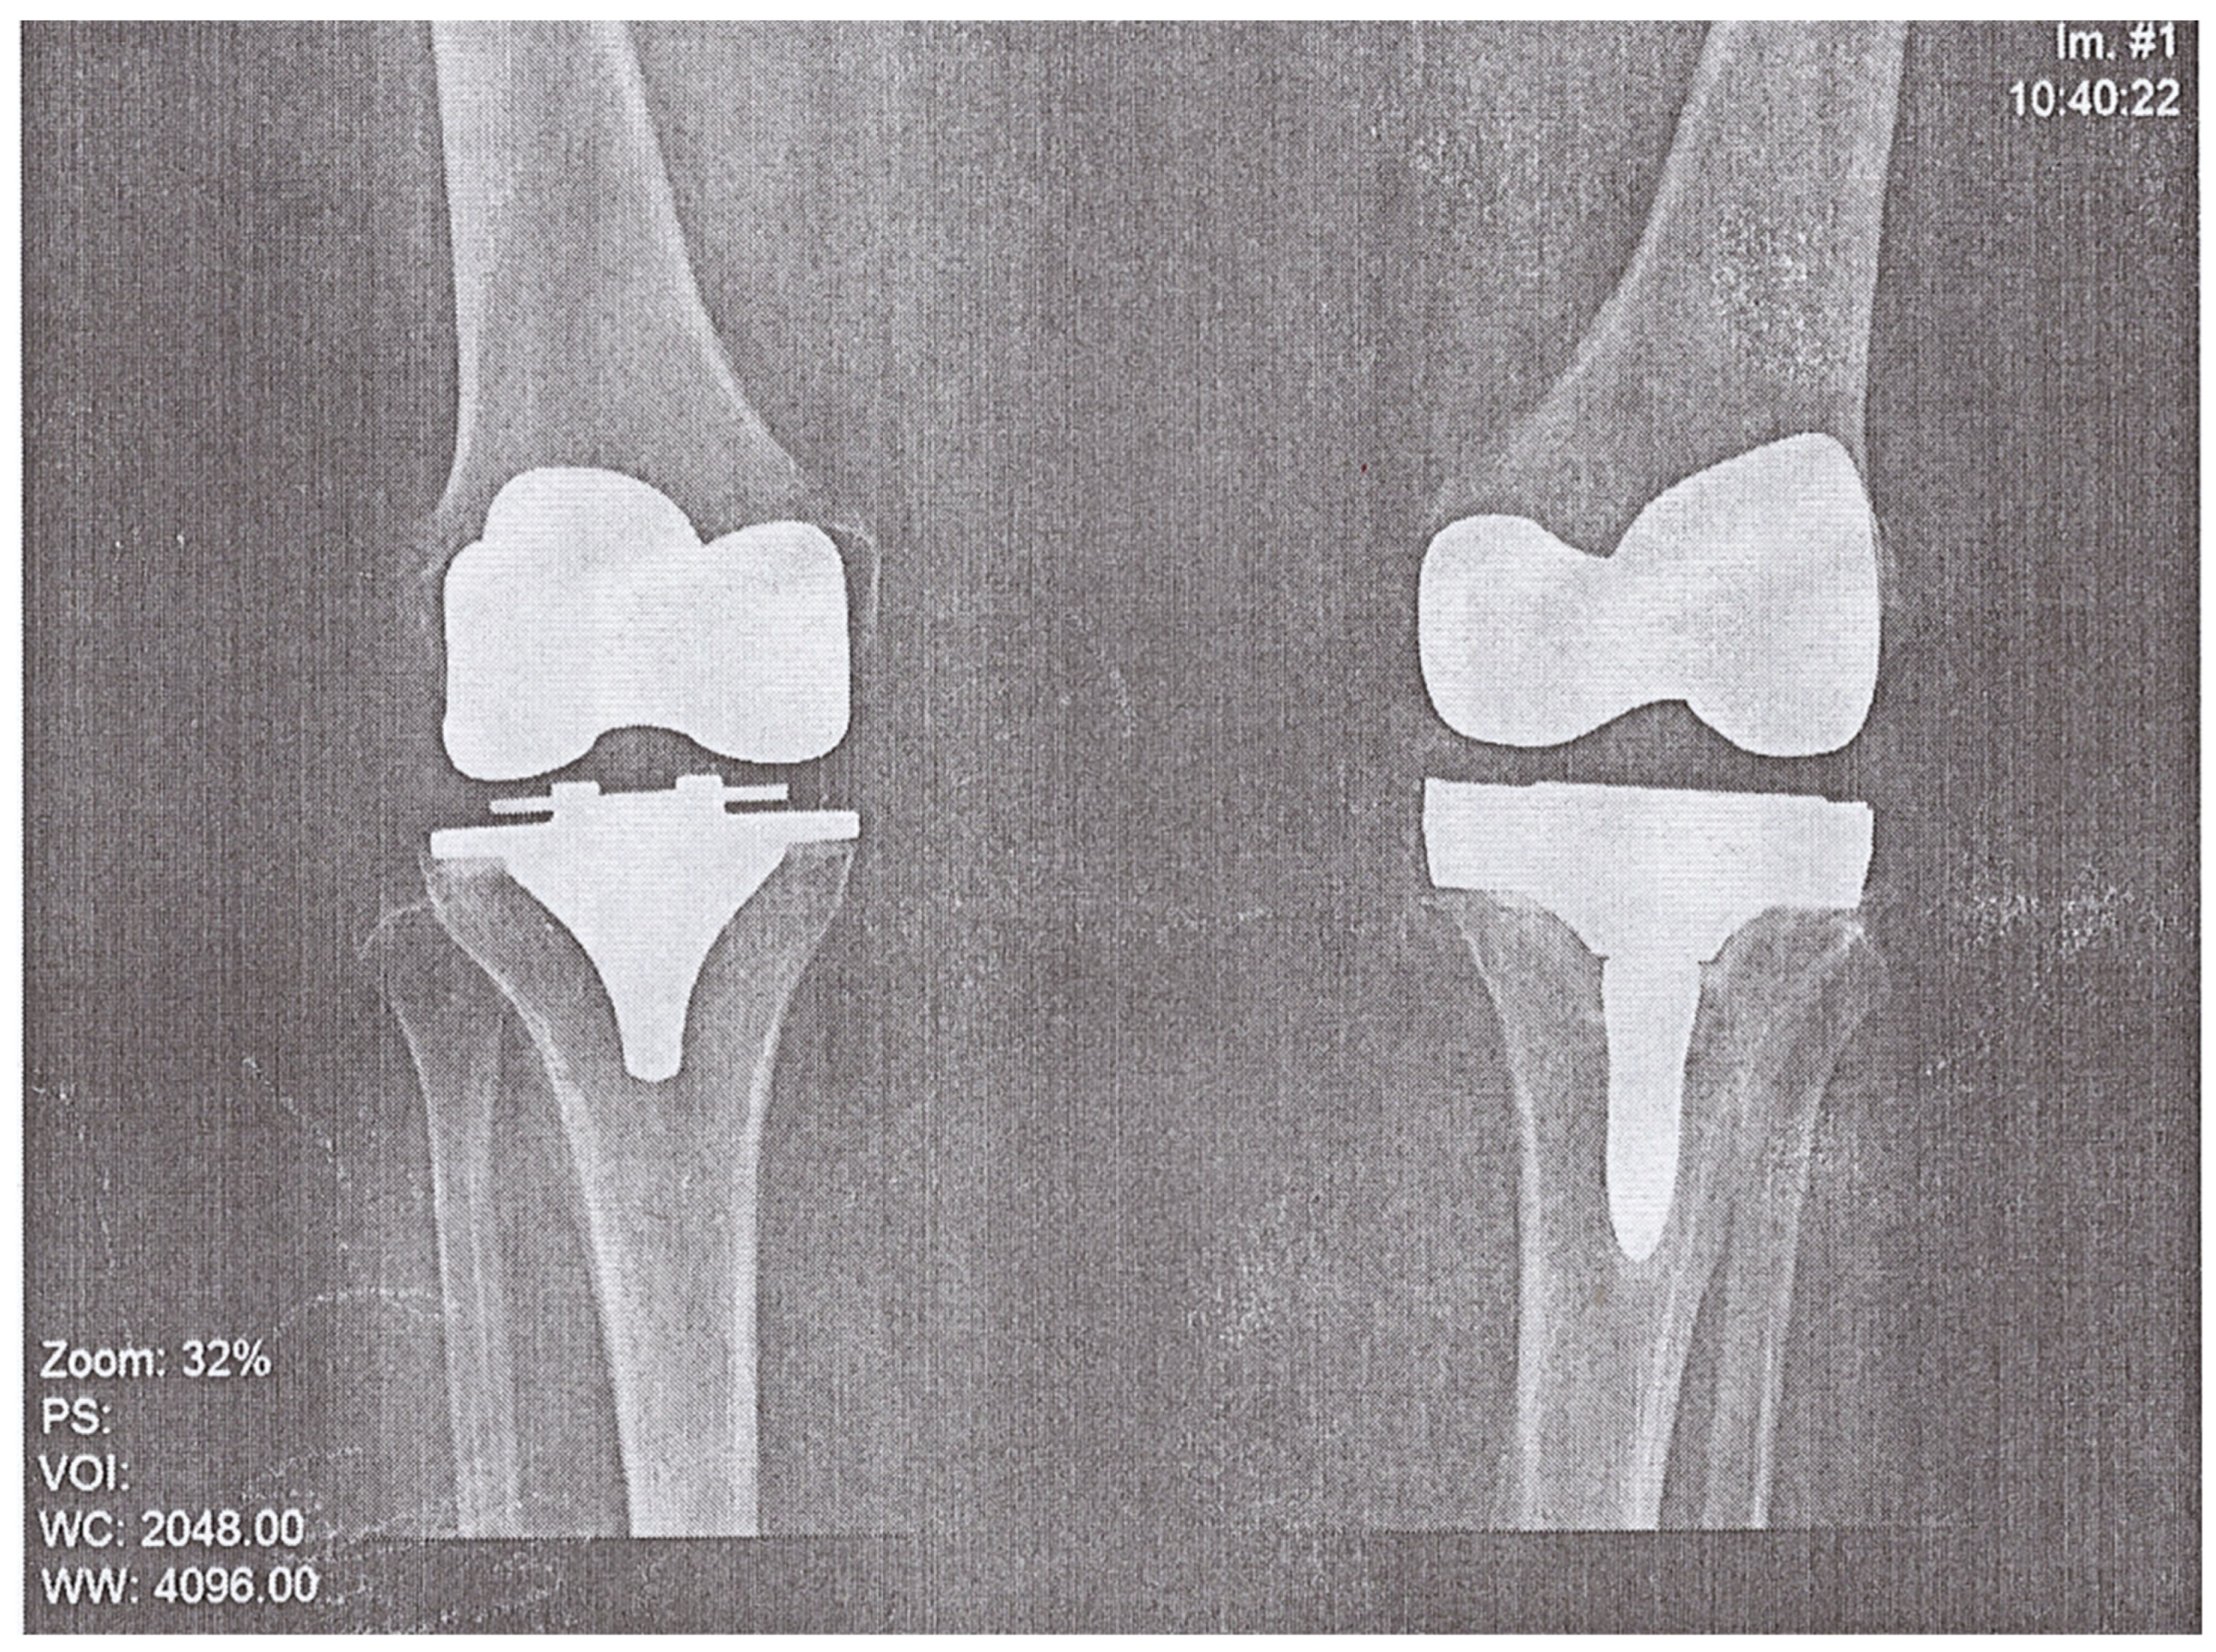

A 74-year-old woman presented to the Emergency Department of a university hospital with left knee pain for the past 2 months. The patient’s medical history revealed a previous left knee alloplasty (3 years prior) with a Stryker Triathlon endoprosthesis, bilateral gonarthrosis, left bundle branch block, chronic atrial fibrillation, an ischemic cerebral infarction (1 year prior), and a right knee alloplasty. Blood results showed no abnormalities other than an elevated neutrophil and monocyte percent (74.2% and 8.3%, respectively) and an elevated CRP of 106.79 mg/L. Septic obturation of the left knee endoprosthesis was diagnosed based on clinical presentation, blood work, and radiography findings (Figure 4 and Figure 5), leading to a re-alloplasty of the left knee.

Figure 4.

AP radiography, pre-operative, of suspected left knee PJI.

Figure 5.

Lateral radiography, pre-operative, of suspected left knee PJI.